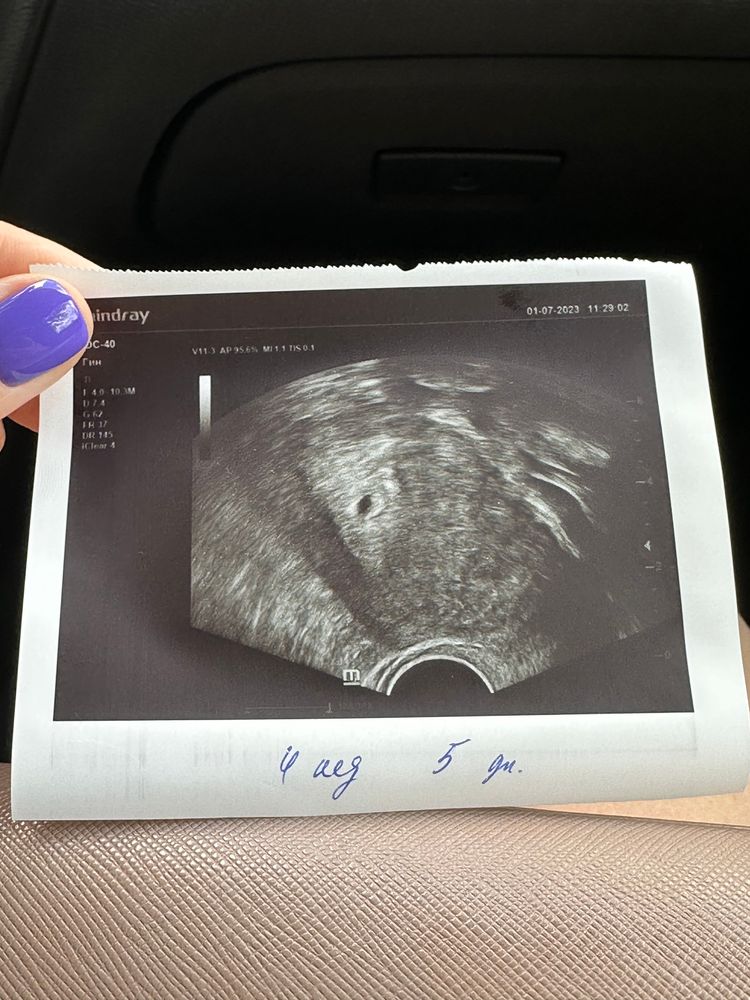

Сегодня была на УЗИ и репродуктолог сказала и написала в заключении 4 недели 5 дней (то есть она отняла 2 недели от даты подсадки). Что думаете?

По узи увидели ПЯ 7 мм, сказала все хорошо, соответствует сроку. Через неделю поедем снова.